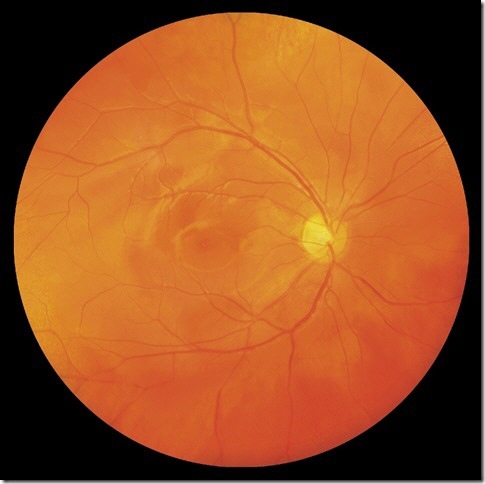

• Photographie

kann Befunde am vorderen Augenabschnitt wie auch an der Netzhaut (Fundus) objektiv dokumentieren und dient so der Verlaufskontrolle über die Zeit.

• Fluoreszenz Angiographie

ermöglicht eine detaillierte Aussage über den Durchblutungsgrad der Netzhaut und läßt neugebildete Gefäße sowie das Eindringen von Flüssigkeit aus den Blutgefäßen in die Netzhautschichten (Ödem) erkennen.